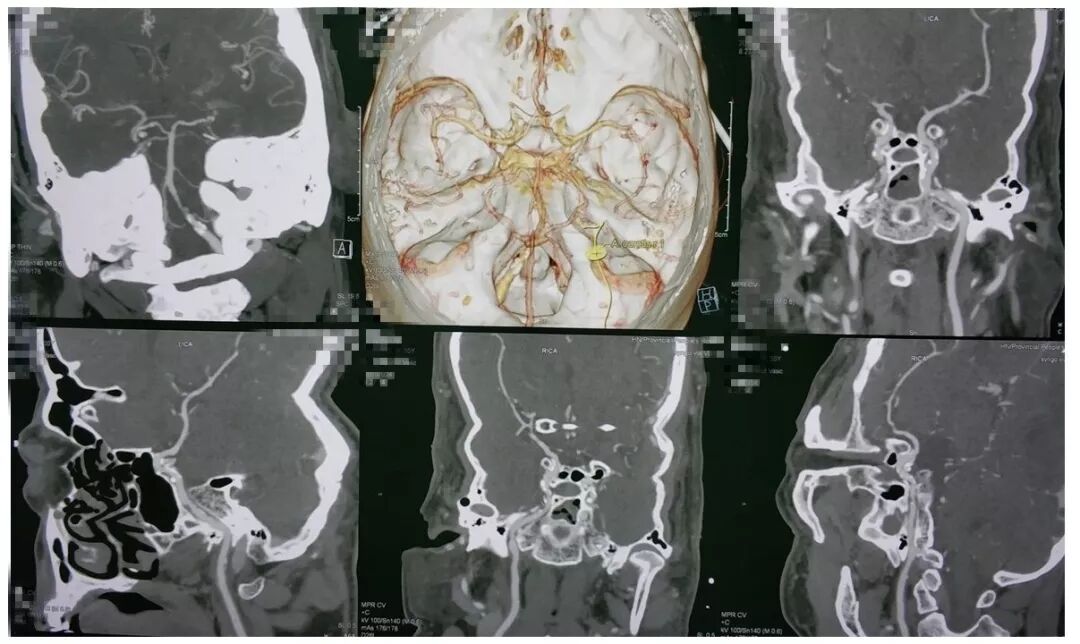

今天为大家分享的是《贝朗时间》第五十一期,由河南省人民医院神经外科步星耀教授团队带来的:脑干海绵状血管瘤伴出血手术病例分享,欢迎阅读、分享!